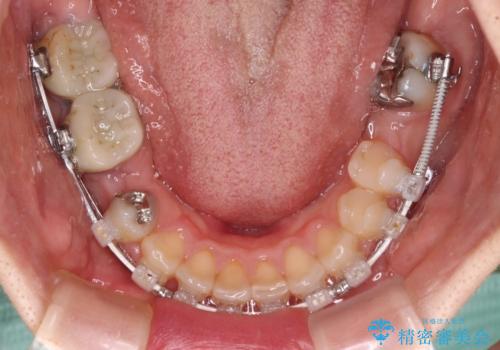

- ハーフリンガル

目立たないハーフリンガル矯正を希望され、裏側装置はどうしても清掃性が低下し、むし歯発生のリスクが高まるため、矯正治療前にしっかりとむし歯治療を行い、矯正治療後にセラミックによる補綴治療を行うこととしました。

抜歯したスペースがなかなか閉じず、治療に時間はかかりましたが、術前術後のむし歯治療と合わせて3年10ヶ月で治療を終えることができました。